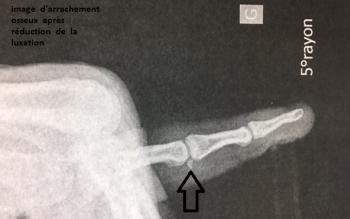

Le diagnostic est clinique, mais des radiographies du doigt de face et de profil seront réalisées à la recherche de pathologie associée (fracture arrachement...). En cas de doute, on pourra réaliser une échographie ou une IRM du doigt.

Ce n’est qu’après échec du traitement orthopédique avec doigt toujours en flexion, ou si le tendon est désinséré avec arrachement osseux (subluxation palmaire de la dernière phalange à la radiographie) ou plaie avec section tendineuse qu’un traitement chirurgical sera proposé.

En cas de rupture simple tendineuse, sans arrachement osseux, la réparation du tendon extenseur s’effectue par suture après réalisation d’une incision transversale ou sinueuse (parfois dermoténodèse surtout dans les cas d’échec de traitement orthopédique). Elle consiste en une suture des deux extrémités du tendon par points en X avec réinsertion du fragment osseux. S’il existe un arrachement osseux, une mini-broche sera introduite pour fixer le fragment. Une immobilisation de six semaines sera nécessaire.